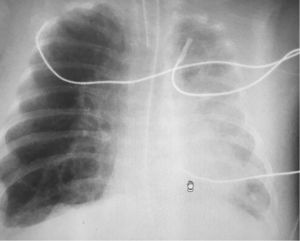

Paciente de 4 meses de edad, exprematuro de 24 semanas de gestación y con displasia broncopulmonar grave, conectado a ventilación mecánica (modalidad presión control con PIP 25cmH2O, PEEP 5,5cmH2O, FR 35rpm y FiO2 30%). El día que describimos, el paciente precisaba FiO2 de hasta el 50% y en la radiografía de tórax (fig. 1) mostraba hiperinsuflación intensa del hemitórax derecho y ausencia de deslizamiento pulmonar en la ecografía pulmonar (fig. 2). Dada la evolución de los pacientes con displasia broncopulmonar hacia la compresión dinámica de la vía aérea distal, se decidió incrementar progresivamente PEEP, sin mejoría ecográfica hasta llegar a una PEEP de 10cmH2O, donde se evidenció reaparición del deslizamiento pleural (fig. 3), y en la radiografía de tórax resolución parcial de la sobredistensión (fig. 4).